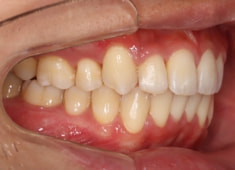

治療前

治療開始時